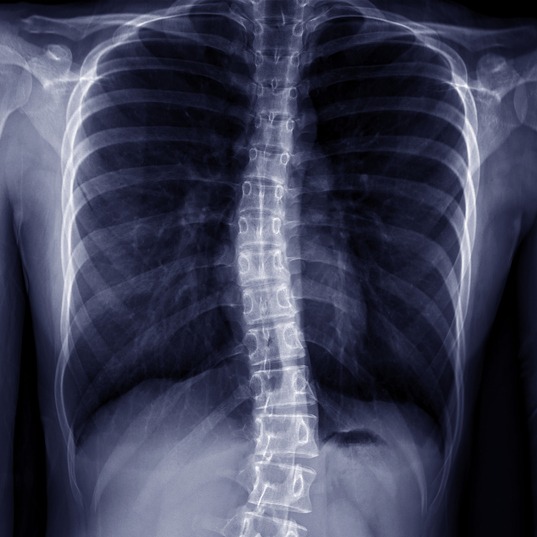

La scoliosi è un’alterazione della normale morfologia della colonna vertebrale, caratterizzata da una deviazione laterale più o meno accentuata della stessa.

La diagnosi della scoliosi avviene tramite visita clinica ed accurato esame obiettivo, finalizzato ad evidenziare eventuali anomalie della colonna vertebrale, riconducibili a patologia scoliotica.

Qualora sussistano i parametri per una scoliosi significativa, lo specialista può prescrivere un esame radiografico della colonna con corretta misurazione del grado di scoliosi e procedere poi alla somministrazione del trattamento più adeguato.